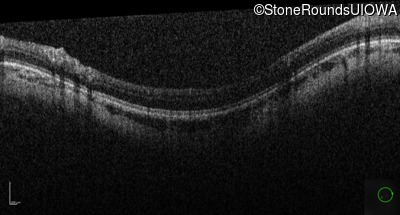

Optical Coherence Tomography - Right - 10/160 +1 sc

Exemplar / OCT Stack

Optical Coherence Tomography - Left - 10/200 sc